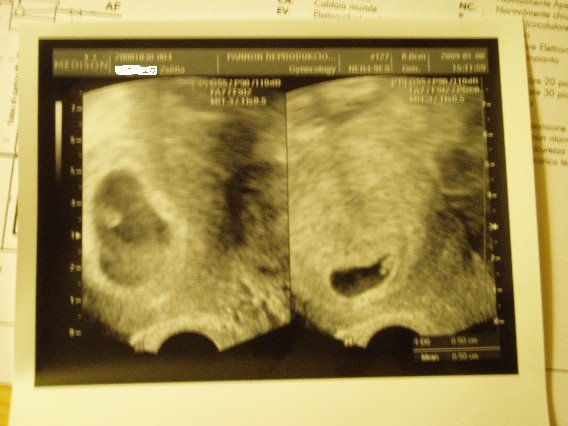

2 hét múlva kell menni, és ugyan akkorák. Mindjárt teszem a képet, már nem fértek rá, külön vannak fotózva és a nagyítás miatt nem ugyanakkorának tűnnek a képen.

Nagon örülünk. A férjem is bent volt, látta, hallotta a szívdobogást! :lol:

Ugyanilyen szép képet várok ám Tőled!!! :lol: Köszi

És akkor a kép, bocsi, bénán fényképeztem:

Zsófi! Sztem külön csodálatos, hogy a két babus teljesen egyforma méretű!!! "Mint két tojás!" :lol: :lol: :lol:

Zsofi! Gratulálok a két kis szívhanghoz, ja és a kép és gyönyörűséges.